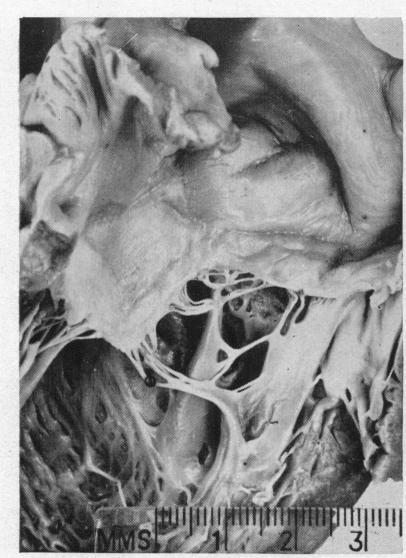

DAVIES J N, BALL J D

Br Heart J. 1955 Jul;17(3):337-59. doi: 10.1136/hrt.17.3.337.